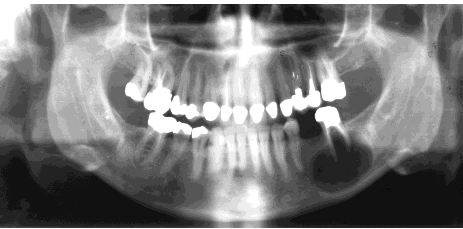

What’s an ameloblastoma?

May mimic other radiolucencies.

What’s a unicystic ameloblastoma?

Account for ~15% of Ameloblastoma. Equal distribution between maxilla and mandible. Usually unilocular associated with the crown of an un erupted tooth peak age 35 years.